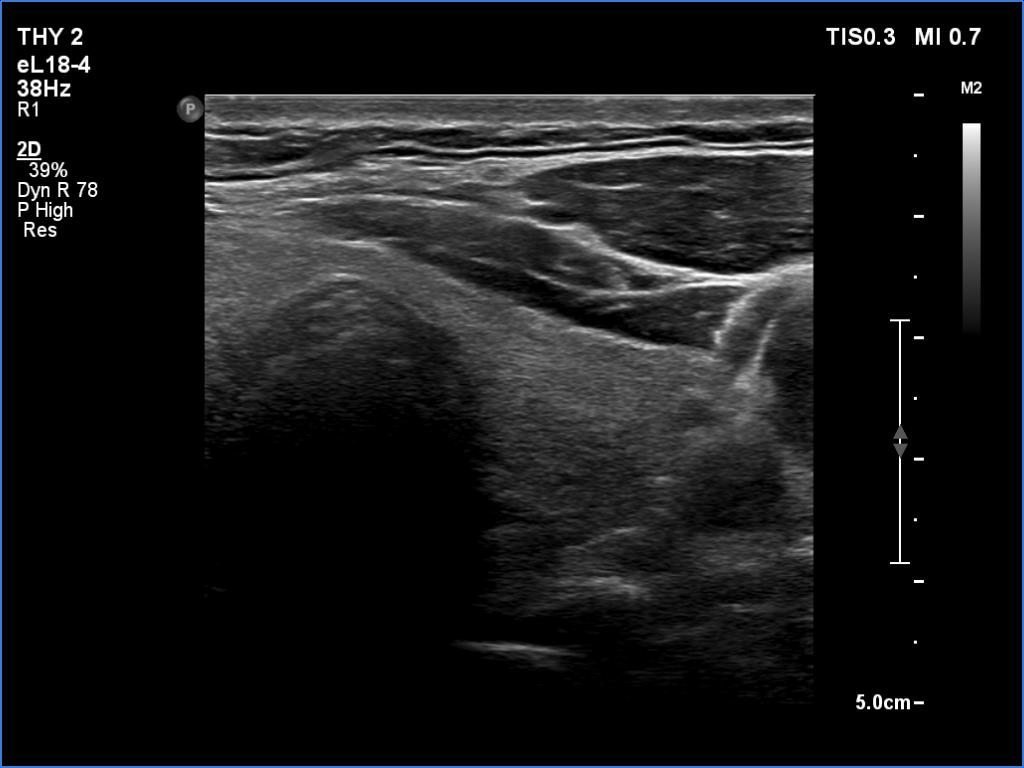

Ultrasonography. The thyroid was echonormal and had two cystic lesions in the left lobe. With higher frequency, the dorsal part of both lobes presented with hypoechoic blurred areas. With frequency decreased, these areas have disappeared.

Comment. This case illustrated the well-known inverse relation between penetrance and resolution. Better the former worst the latter and conversely. This has particular and practical importance if we examine obese patients using high-end equipment with high frequency. In such patients the obesity can significantly worsen the penetrance. This can be solved by decreasing the frequency and remove all software harmonization.